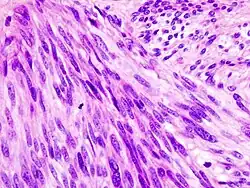

![]() | |

| Histopathologic image of gastrointestinal stromal tumor of the stomach. Hematoxylin-eosin stain. | |

The definitive diagnosis is made with a biopsy, which can be obtained endoscopically, percutaneously with CT or ultrasound guidance or at the time of surgery. A biopsy sample will be investigated under the microscope by a pathologist physician. The pathologist examines the histopathology to identify the characteristics of GISTs (spindle cells in 70-80%, epitheloid aspect in 20-30%). Smaller tumors can usually be confined to the muscularis propria layer of the intestinal wall. Large ones grow, mainly outward, from the bowel wall until the point where they outstrip their blood supply and necrose (die) on the inside, forming a cavity that may eventually come to communicate with the bowel lumen.

When GIST is suspected—as opposed to other causes for similar tumors—the pathologist can use immunohistochemistry (specific antibodies that stain the molecule CD117 [also known as c-KIT] —see below). 95% of all GISTs are CD117-positive (other possible markers include CD34, Discovered On GIST-1 (DOG1),[19] desmin, and vimentin). Other cells that show CD117 positivity are mast cells.

If the CD117 stain is negative and suspicion remains that the tumor is a GIST, the newer antibody DOG1 can be used. Also, sequencing of KIT and PDGFRA can be used to prove the diagnosis.